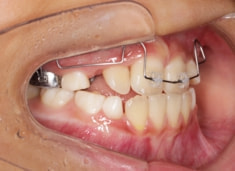

FX(フェイシャルアキシス)は85度なので東洋人の平均値に近く、下顎が前方に過剰成長するリスクは強くはありません。

しかしやはり上顎は劣成長で、下顎が優位な状態ではあります。

上下顎のギャップはありますが、顔面自体の幅径は良好な値を示していますので、スペース不足は拡大することによって解決できポテンシャルはあると考えられます。

左右の非対称もさほど強くありません。

骨年齢は実年齢よりも低めなので、今後下顎の旺盛な成長が見込まれます。

検査時のレントゲン分析では、上下顎の関係は、上顎の劣成長があり下顎前突傾向という値がでておりましたが、前歯ジャンプ後はフェイスマスクの効果もあり、上下顎の関係は正常化しています。

上顎が若干優位になっていますので、今後の下顎の成長のための貯金になっているくらいです。